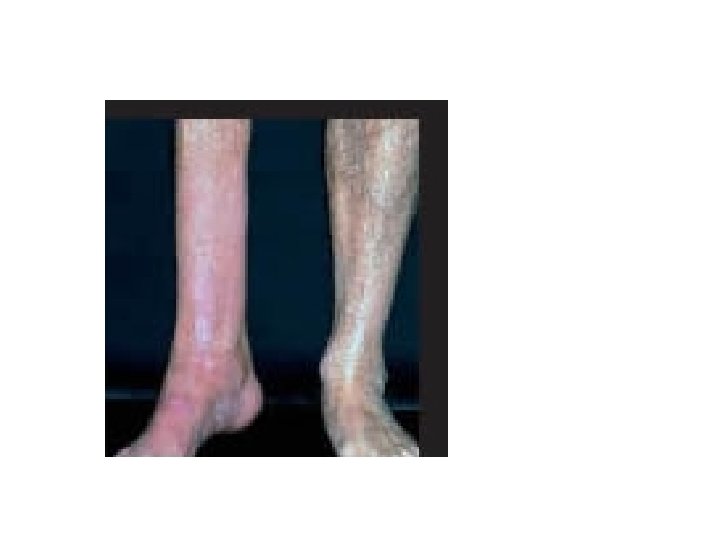

• Kullanılmama atrofisi: Alçıya alınan ekstremitede kas atrofisi ve osteoporoz • Denervasyon atrofisi: Travmatik sinir kesisi • Kan akımı azalmasına bağlı atrofi: İskemi Ateroskleroz ileri yaşta beyin atrofisi • Yetersiz beslenmeye bağlı atrofi • Endokrin stimülasyon kaybına bağlı atrofi: Menopozda endometrium atrofisi, vaginal epitel atrofisi • Senil atrofi: Yaşlanma ile kalp ve beyinde hücre kaybı • Basınç atrofisi: Tümörler çevre dokuya basınç yaparak atrofiye sebep olur.